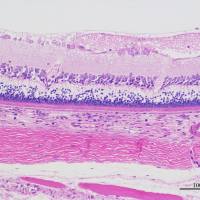

细胞库 / 细胞培养、技术服务